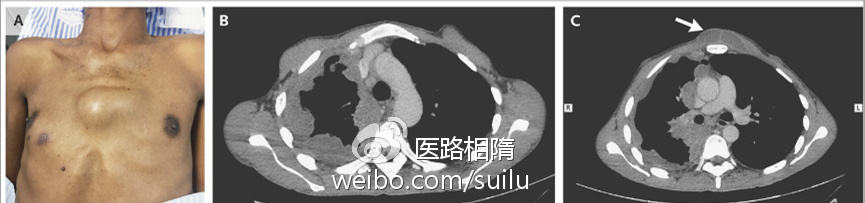

自溃性脓胸是结核性脓胸常见的并发症。结核性脓胸的壁层胸膜破裂,自发排出其内容物,可进入许多组织,最常见的额是胸壁皮下组织。